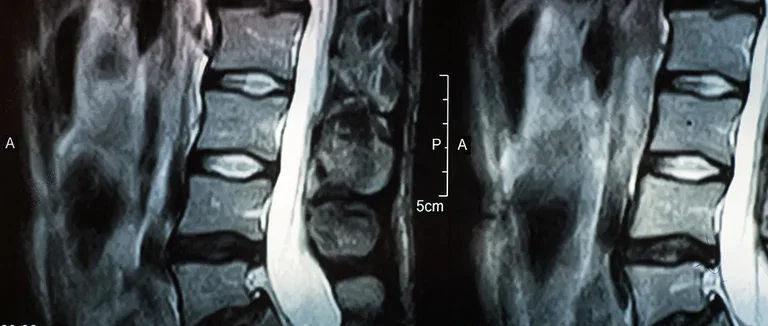

Il est important de comprendre la hernie discale pour mieux choisir le traitement. Cette condition affecte les disques entre les vertèbres de la colonne vertébrale.

La colonne vertébrale est faite de vertèbres séparées par des disques. Ces disques absorbent les chocs et aident à bouger la colonne. Chaque disque a un noyau gélatineux entouré d'un anneau fibreux.

Mécanisme de la Hernie Discale

Une hernie discale se produit quand un disque se déplace ou se rompt. Cela crée une saillie qui peut presser les nerfs. Cela peut causer des douleurs, des engourdissements ou des faiblesses dans le dos, les jambes ou les bras.